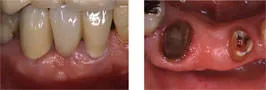

歯槽堤増大術

Before

After

抜歯後の骨吸収によりこのままブリッジを入れてしまうとこの部位だけ歯が長くなってしまい清掃性、審美性共に不良なものになってしまう。組織を移植することにより歯茎の形態を改善させ理想的な形態のブリッジを装着することが出来ました。